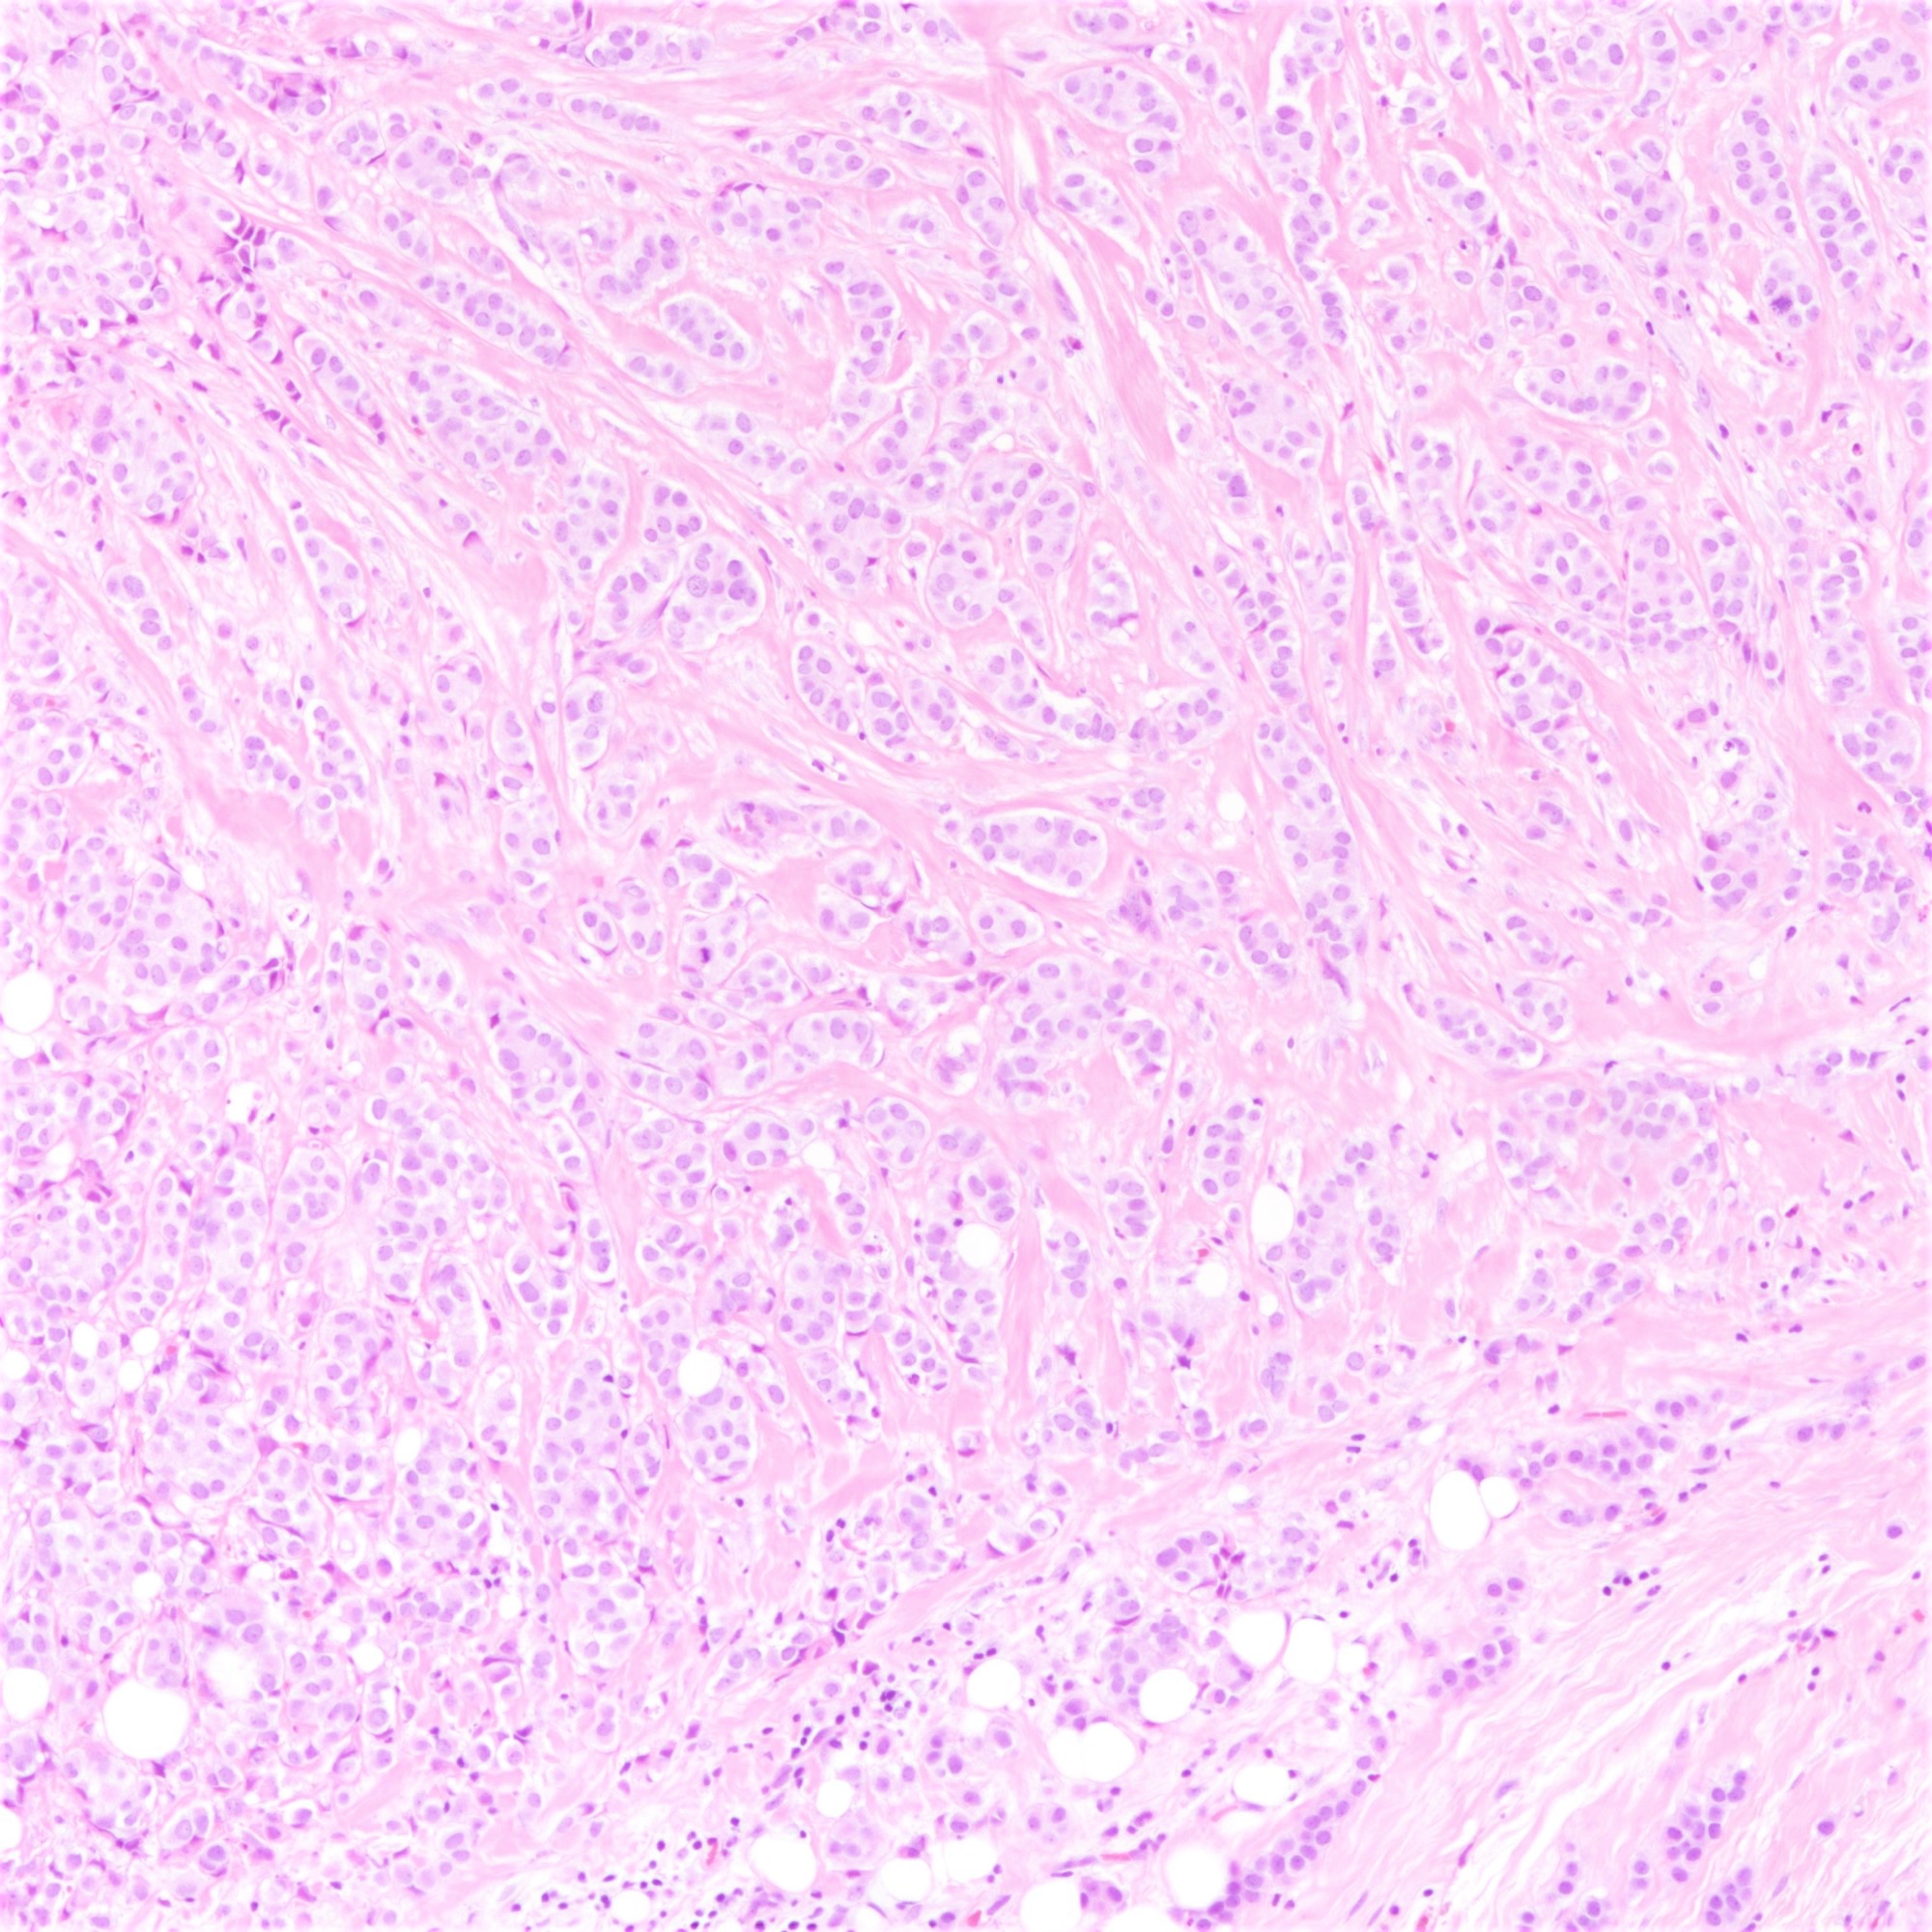

Microscopic (histologic) description

- Tumor cells arranged in single files, cords and single cells (Breast Cancer Res 2015;17:12)

- Can be arranged concentrically around normal ducts, giving a targetoid appearance

- Tumor cells discohesive, small, monomorphic and lacking marked atypia

- Round or notched ovoid nuclei, usually grade 1 or 2 nuclear score

- Scant cytoplasm, occasional with intracytoplasmic lumen

- Mitosis infrequent

- Desmoplastic reaction and necrosis uncommon

- Requires high index of suspicion for metastasis

Microscopic (histologic) images